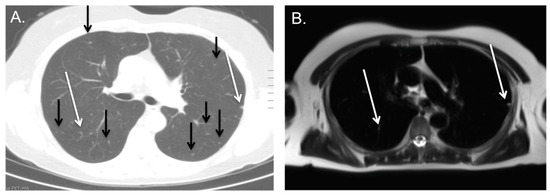

3.3. Indeterminate Lung Nodule Detection